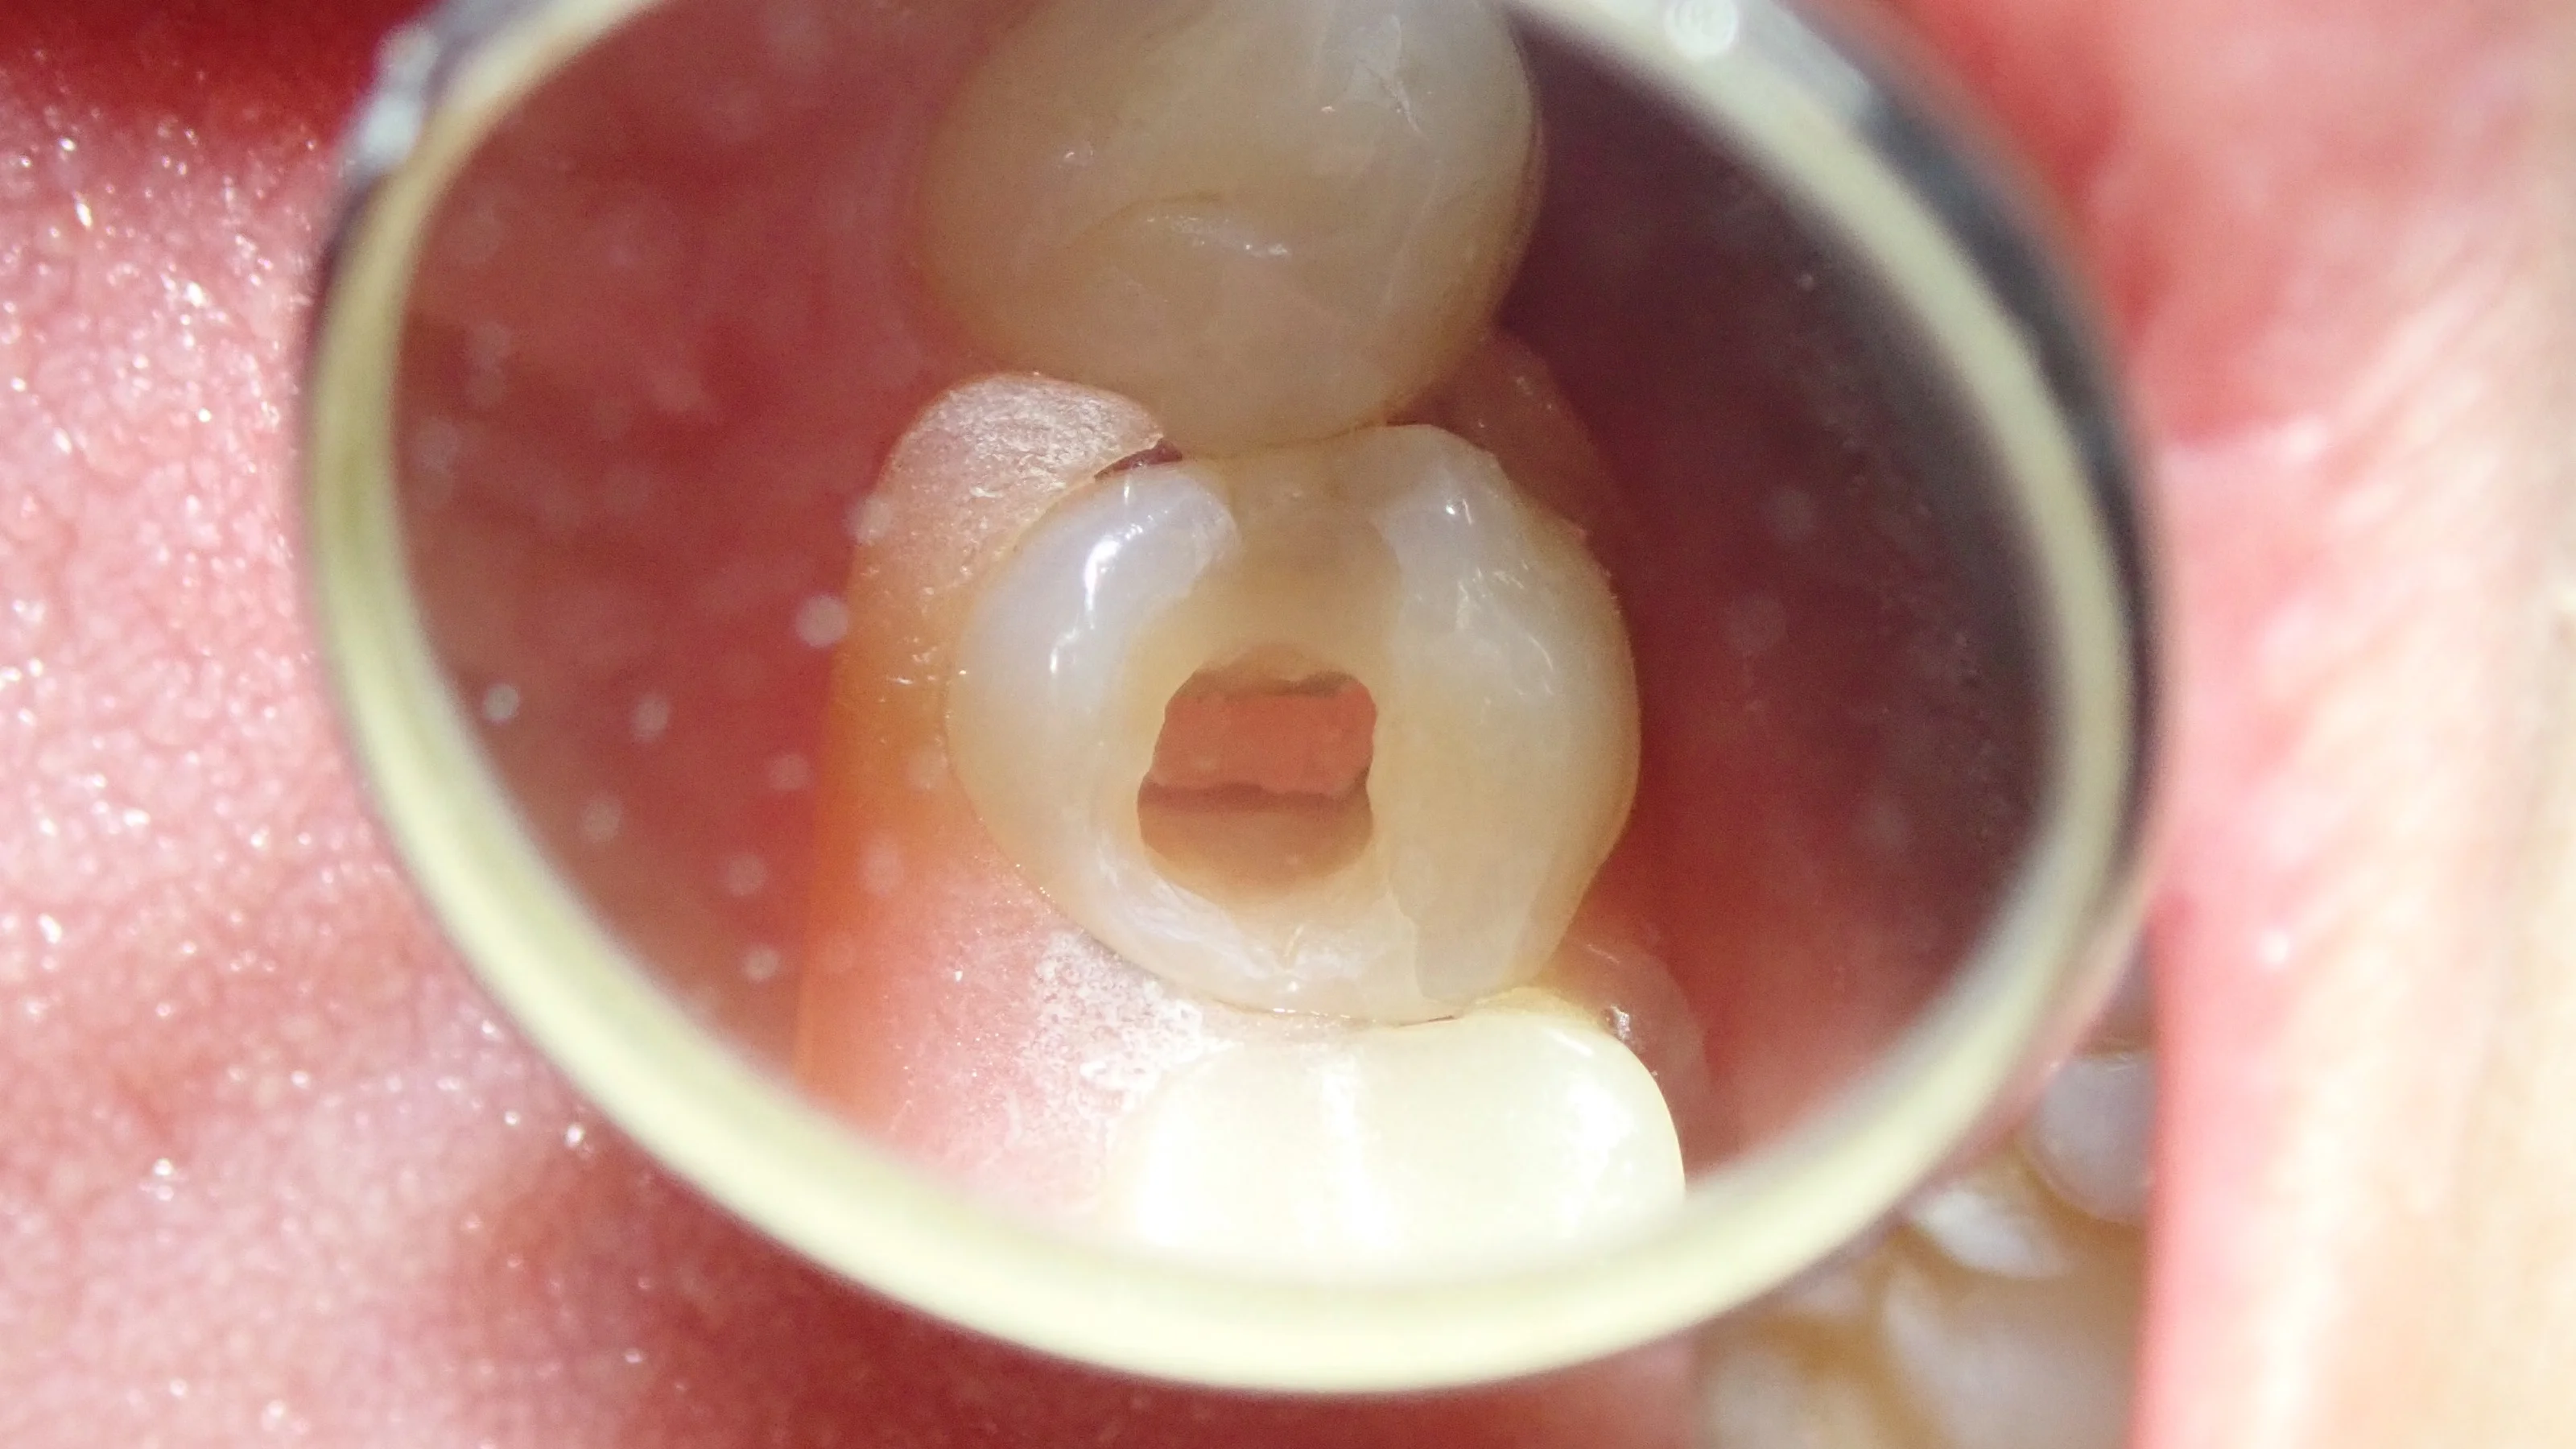

術前の状態です。

元々白い詰め物が詰められていますが、亀裂が入っており、その付近から虫歯が黒く透けて見えています。